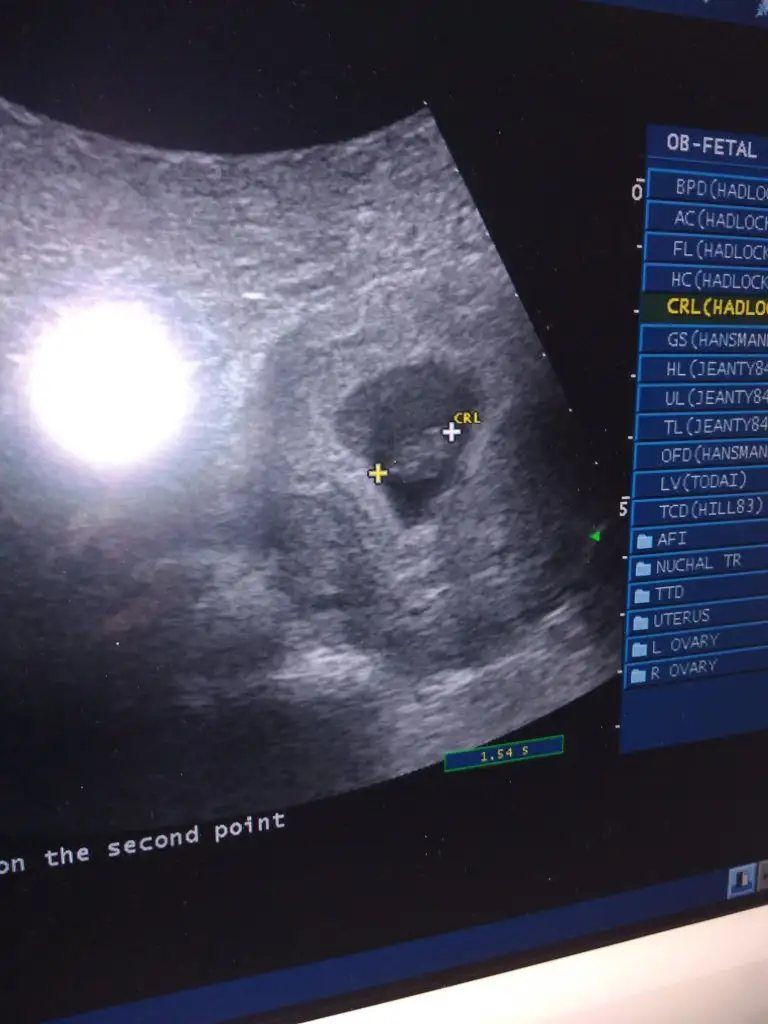

bnmde 5 +4 ken ultrasyonda baktırdım daha minik duruyodu benmki :)5+2 haftalık 14.44 mm yazıyo kağıtta

6+4 de kese içindeki bebek görünüyo maşallah baya büyük bnmde bugun tam 6 hafta oldu cok merak ediyorum bu kadar büyümüşmüdür kalp atışlarıonı duyabildinizmiKızlar tahmini olan var mı bildiğiniz fasulye gibi 6+4

Evet 6+4 de yani o ultrason fotoğrafını aldığımız gün duyduk maşallah güzeldi kalp atışı da6+4 de kese içindeki bebek görünüyo maşallah baya büyük bnmde bugun tam 6 hafta oldu cok merak ediyorum bu kadar büyümüşmüdür kalp atışlarıonı duyabildinizmi